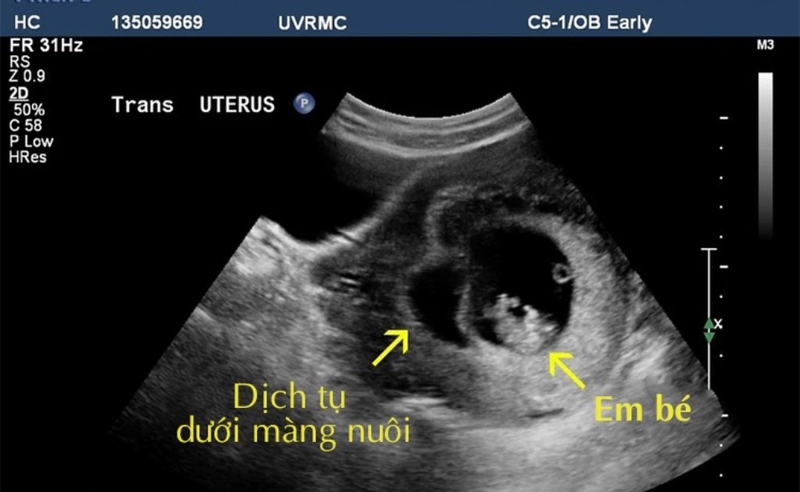

Tụ dịch màng nuôi là thuật ngữ y học dùng để chỉ tình trạng có sự xuất hiện cục máu tại một khoảng ở giữa nhau thai với tử cung người mẹ. Lớp máu này làm cho túi thai bị tách một phần ra khỏi tử cung và gây ảnh hưởng đến tình trạng sức khoẻ của thai nhi. Tụ dịch màng nuôi được đánh giá là một trong những biến chứng thai kỳ khá thường gặp, chiếm tỷ lệ khoảng 16 – 25% trong các trường hợp phụ nữ mang thai.

Vậy tụ dịch màng nuôi 27mm là gì? Các bác sĩ thường đánh giá nguy cơ đối với thai nhi thông qua tỷ lệ tụ dịch và sự phát triển của dịch tụ. Cụ thể tụ dịch có kích thước nhỏ là từ 0,5 – 5mm, tụ dịch ở mức độ trung bình là từ 5 – 12mm, tụ dịch có kích thước lớn là trên 12mm. Như vậy, tụ dịch màng nuôi 27mm là tình trạng tụ dịch có kích thước khá lớn, ảnh hưởng nhiều đến sự phát triển của thai nhi.